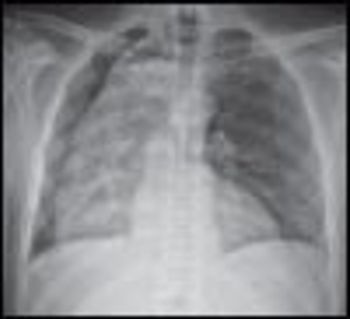

Diastolic heart failure (or HFPEF-heart failure with preserved ejection fraction) is characterized by inadequate myocardial relaxation and diastolic filling ("stiff ventricle"), with heart failure signs and symptoms despite normal ejection fraction. The most common cause is long-standing hypertension.